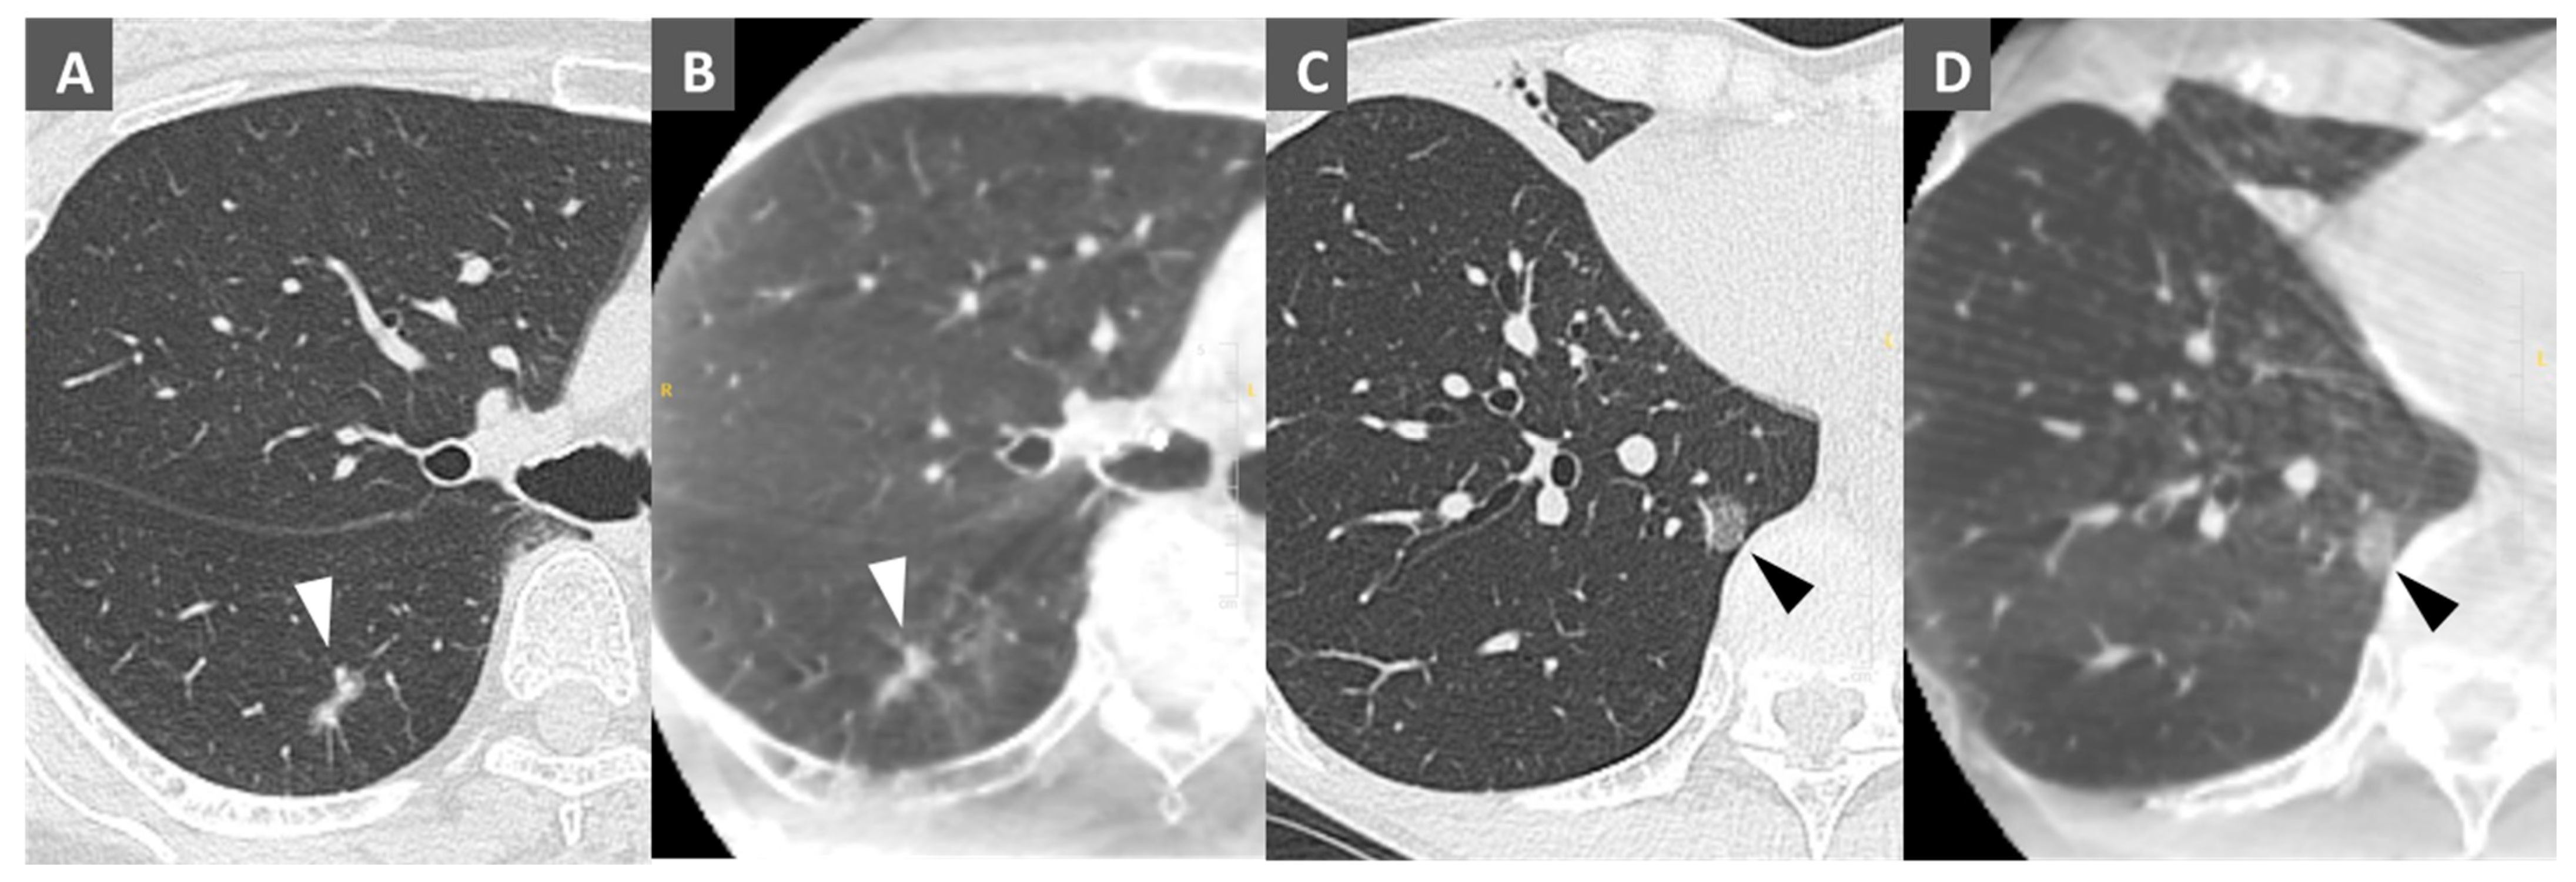

2.4. Bronchoscopic Metallic Coil Marking Procedure

2.5. VATS Resection Technique